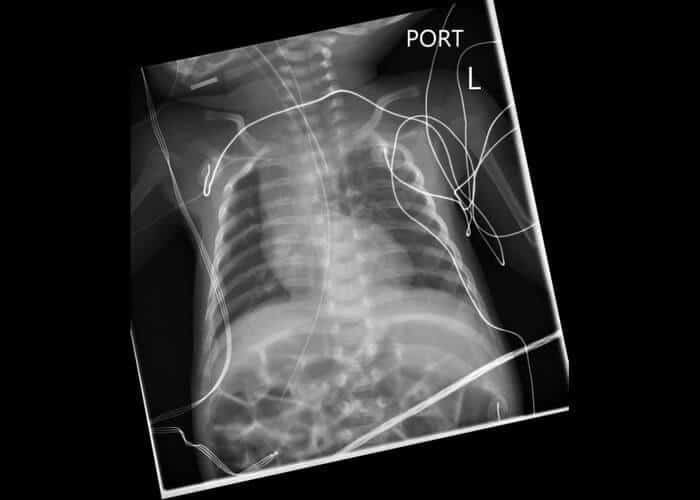

7.

Бригам Нордстром

Многие из наших инструментов поставляются парами, но ни один инструмент не должен состоять только из трех, не говоря уже о четырех или пяти. Девять лет назад с инфекционным заболеванием почек был госпитализирован юрист из Новой Зеландии, которому на тот момент было 28 лет. Обследование его внутренних органов показало, что у него было пять функционирующих почек. Он является единственным человеком в истории, страдающим таким расстройством. Многие задавались вопросом, не хочет ли Бригам продать свои запасные почки и прожить безбедную старость. Однако врачи не советуют этому уникальному пациенту отказываться от своих "помощников" без видимой причины. На самом деле удаление почки может вызвать серьезные повреждения нервной системы, а сама операция всегда сопряжена с риском для жизни и здоровья и предполагает длительную реабилитацию и лечебную диету.